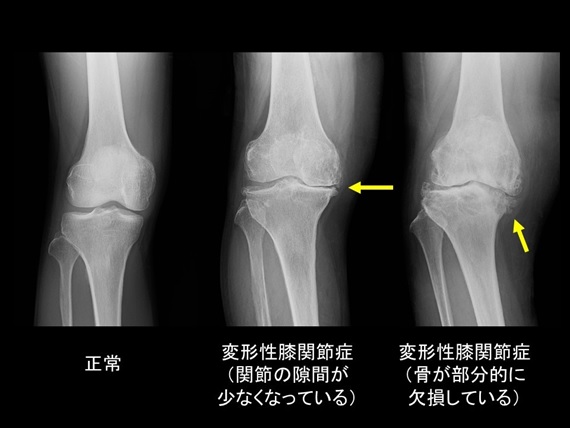

医師は X 線 (X 線撮影) を使用して、骨の変化と膝関節の位置を観察します。これは変形性関節症の診断に役立ちます。

X線では軟骨の画像を撮影することはできません。ただし、骨の間の空間が狭くなることによる軟骨の喪失が明らかになる場合があります。これは、変形性関節症や軟骨が侵食されたその他の関節疾患の最も明白な症状です。医師が骨や軟組織をさらに詳しく観察したい場合は、MRI 検査を紹介することもあります。

X 線写真で確認できる変形性膝関節症の 4 つの兆候には、関節腔の狭小化、骨棘、関節表面の凹凸、皮質下の嚢胞が含まれます。

X 線は、変形性関節症の兆候を特定するために骨の画像を取得する標準的な方法です。